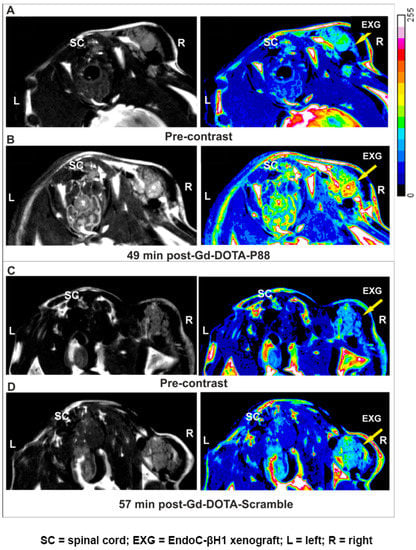

4.7. MRI and Ex Vivo Biodistribution of Gd-DOTA-P88 and Gd-DOTA-Scramble